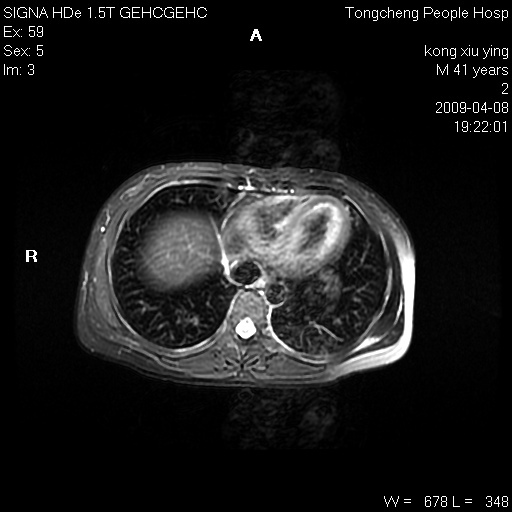

标题: CL1008:【经典】胆囊石榴籽样结石。 [打印本页]

标题: CL1008:【经典】胆囊石榴籽样结石。

女,41岁。健康体检——彩超提示:胆囊显示不清。平素健康,无不适感。

腹部mr扫描及mrcp,图像如下: